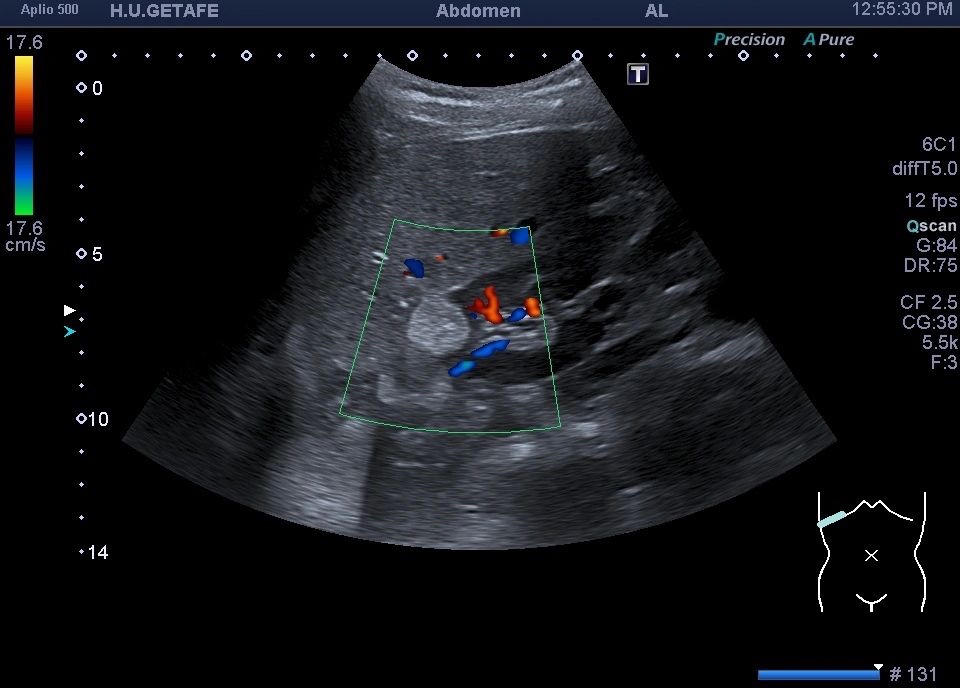

Deben demostrarse siempre en axial y sagital y usar Doppler color y Modo Angio.

Tiene tres partes la palabra AngioMioLipoma. Hace referencia a vascularizacion, músculo y grasa.

Esa es la composición del tumor benigno del riñón por excelencia.